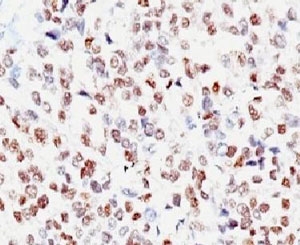

IHC: Formalin-fixed, paraffin-embedded human melanoma stained with MITF antibody (clone MITF/915).

MITF (microphthalmia transcription factor) is a basic helix-loop-helix-leucine-zipper (bHLH-Zip) transcription factor that regulates the development and survival of melanocytes and retinal pigment epithelium, and also is involved in transcription of pigmentation enzyme genes such as tyrosinase TRP1 and TRP2. MITF has been shown to be phosphorylated by MAP kinase in response to c-kit activation, resulting in upregulation of MITF transcriptional activity. Mutations of the MITF gene are associated with the autosomal dominant hereditary deafness and pigmentation condition, Waardenburg Syndrome type 2A. Multiple isoforms of MITF exist, including MITF-A, MITF-B, MITF-C, MITF-H, and MITF-M, which differ in the amino-terminal domain and in their expression patterns. The MITF-M isoform is restricted to the melanocyte cell lineage. This mAb recognizes a nuclear protein, which is expressed in the majority of primary and metastatic epithelioid malignant melanomas as well as in normal melanocytes, benign nevi and dysplastic nevi.